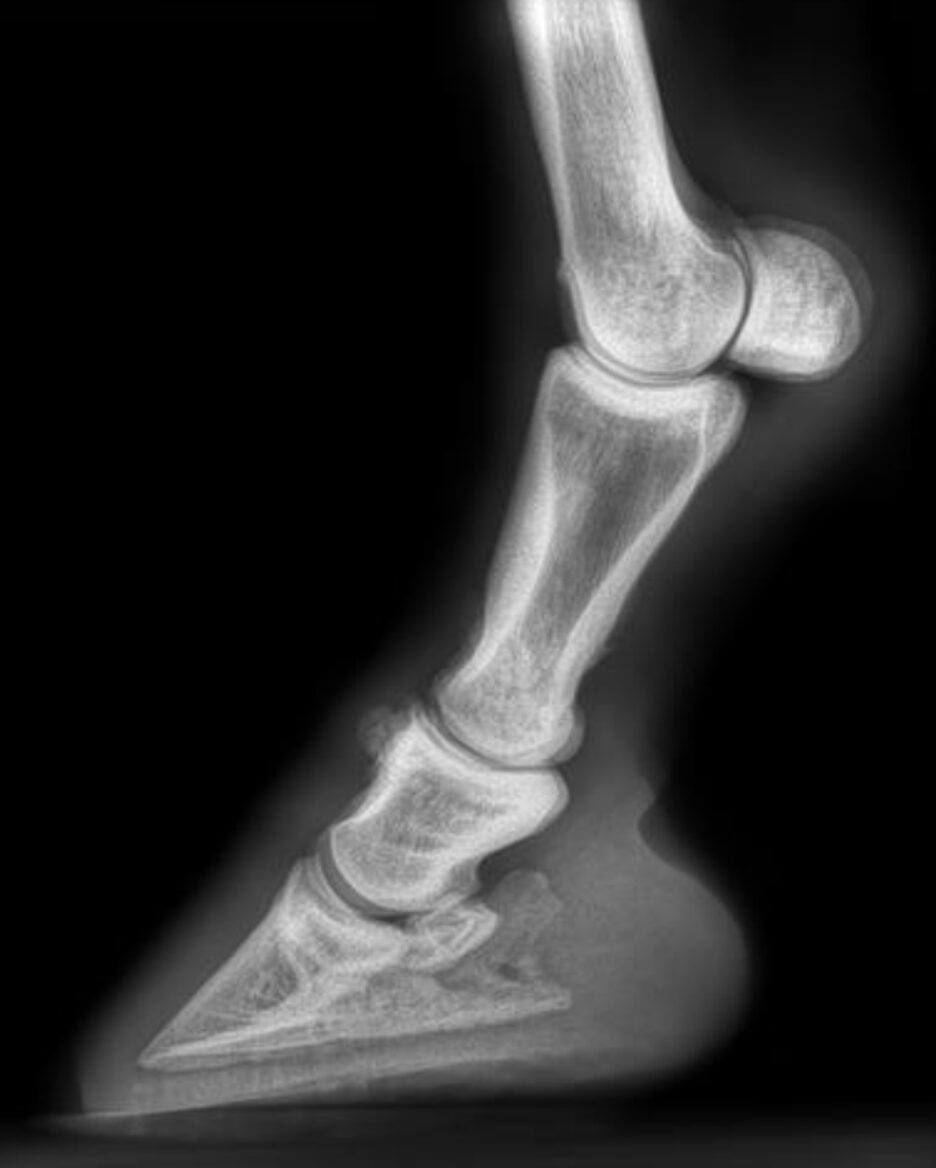

To localize the source of pain, intra-articular analgesia was administered into the left proximal interphalangeal joint. This resulted in complete resolution of the lameness, confirming the pastern joint as the primary source. Radiographs of both distal forelimbs revealed moderate osteoarthritis.